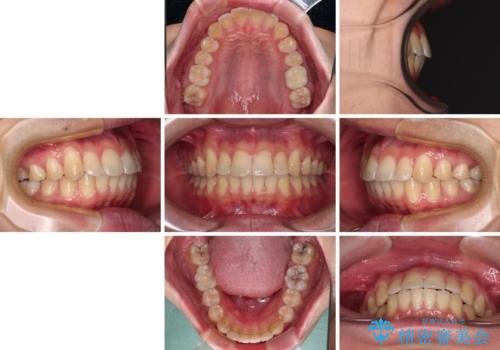

- 上下前歯のデコボコを気にして来院された患者様です。

マウスピース矯正でもワイヤー矯正でも対応可能でしたが、インビザラインによる自己管理が煩わしいとのことで、ワイヤー装置にて矯正治療を行うこととしました。

口元はやや突出感がありましたが抜歯矯正をするほどではないため、舌突出癖を改善するトレーニングをしっかりと行っていただき、現在よりも唇が閉じやすい位置に仕上げていくこととしました。

下顎前歯が思っていた以上に動きが悪く、想定よりも期間がかかってしまいました。

矯正治療後には気になっていた銀歯をセラミックで自然な色に仕上げました。